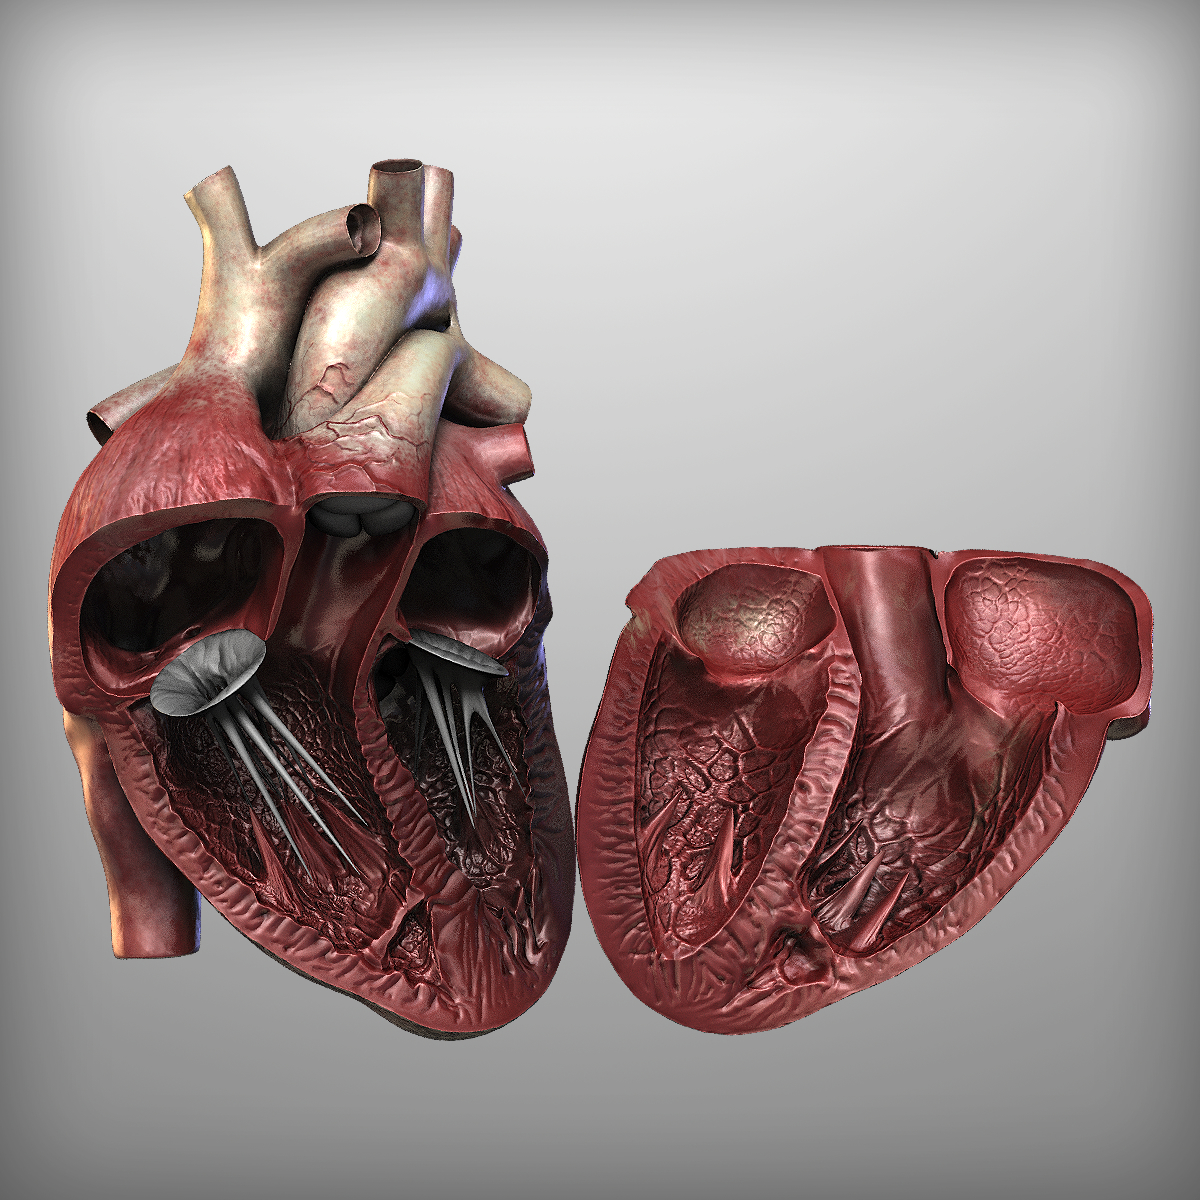

//thebrainstormlab.com/banners/ami_banner.jpgThis is a medical | Heart anatomy drawing, Human  Human Heart Section 3D model | CGTrader

Human Heart Section 3D model | CGTrader  human heart - internal anatomy 3d model

human heart - internal anatomy 3d model  3D Illustration Human Heart 3D Images - Iwish Iwas

3D dissected human heart model - TurboSquid 1361664  10 Realistic Heart Drawings and Tattoos â Simple Human Heart Sketch for 2022 | Do It Before Me

Human Heart Section 3D model | CGTrader  3d human heart

Human Heart Cutaway Anatomy 3D model section | CGTrader  Human Heart by Mutantenmaid on DeviantArt

human heart interior 3d model  Image of Human Heart 3D Illustration | Stock Image MXI28575

3d human heart section  human heart solidworks 3d model

human heart - internal anatomy 3d model  Heart Diagram Human Heart Images Hd 3D - img-Badr